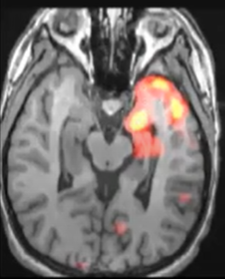

Imagerie de l’épilepsie